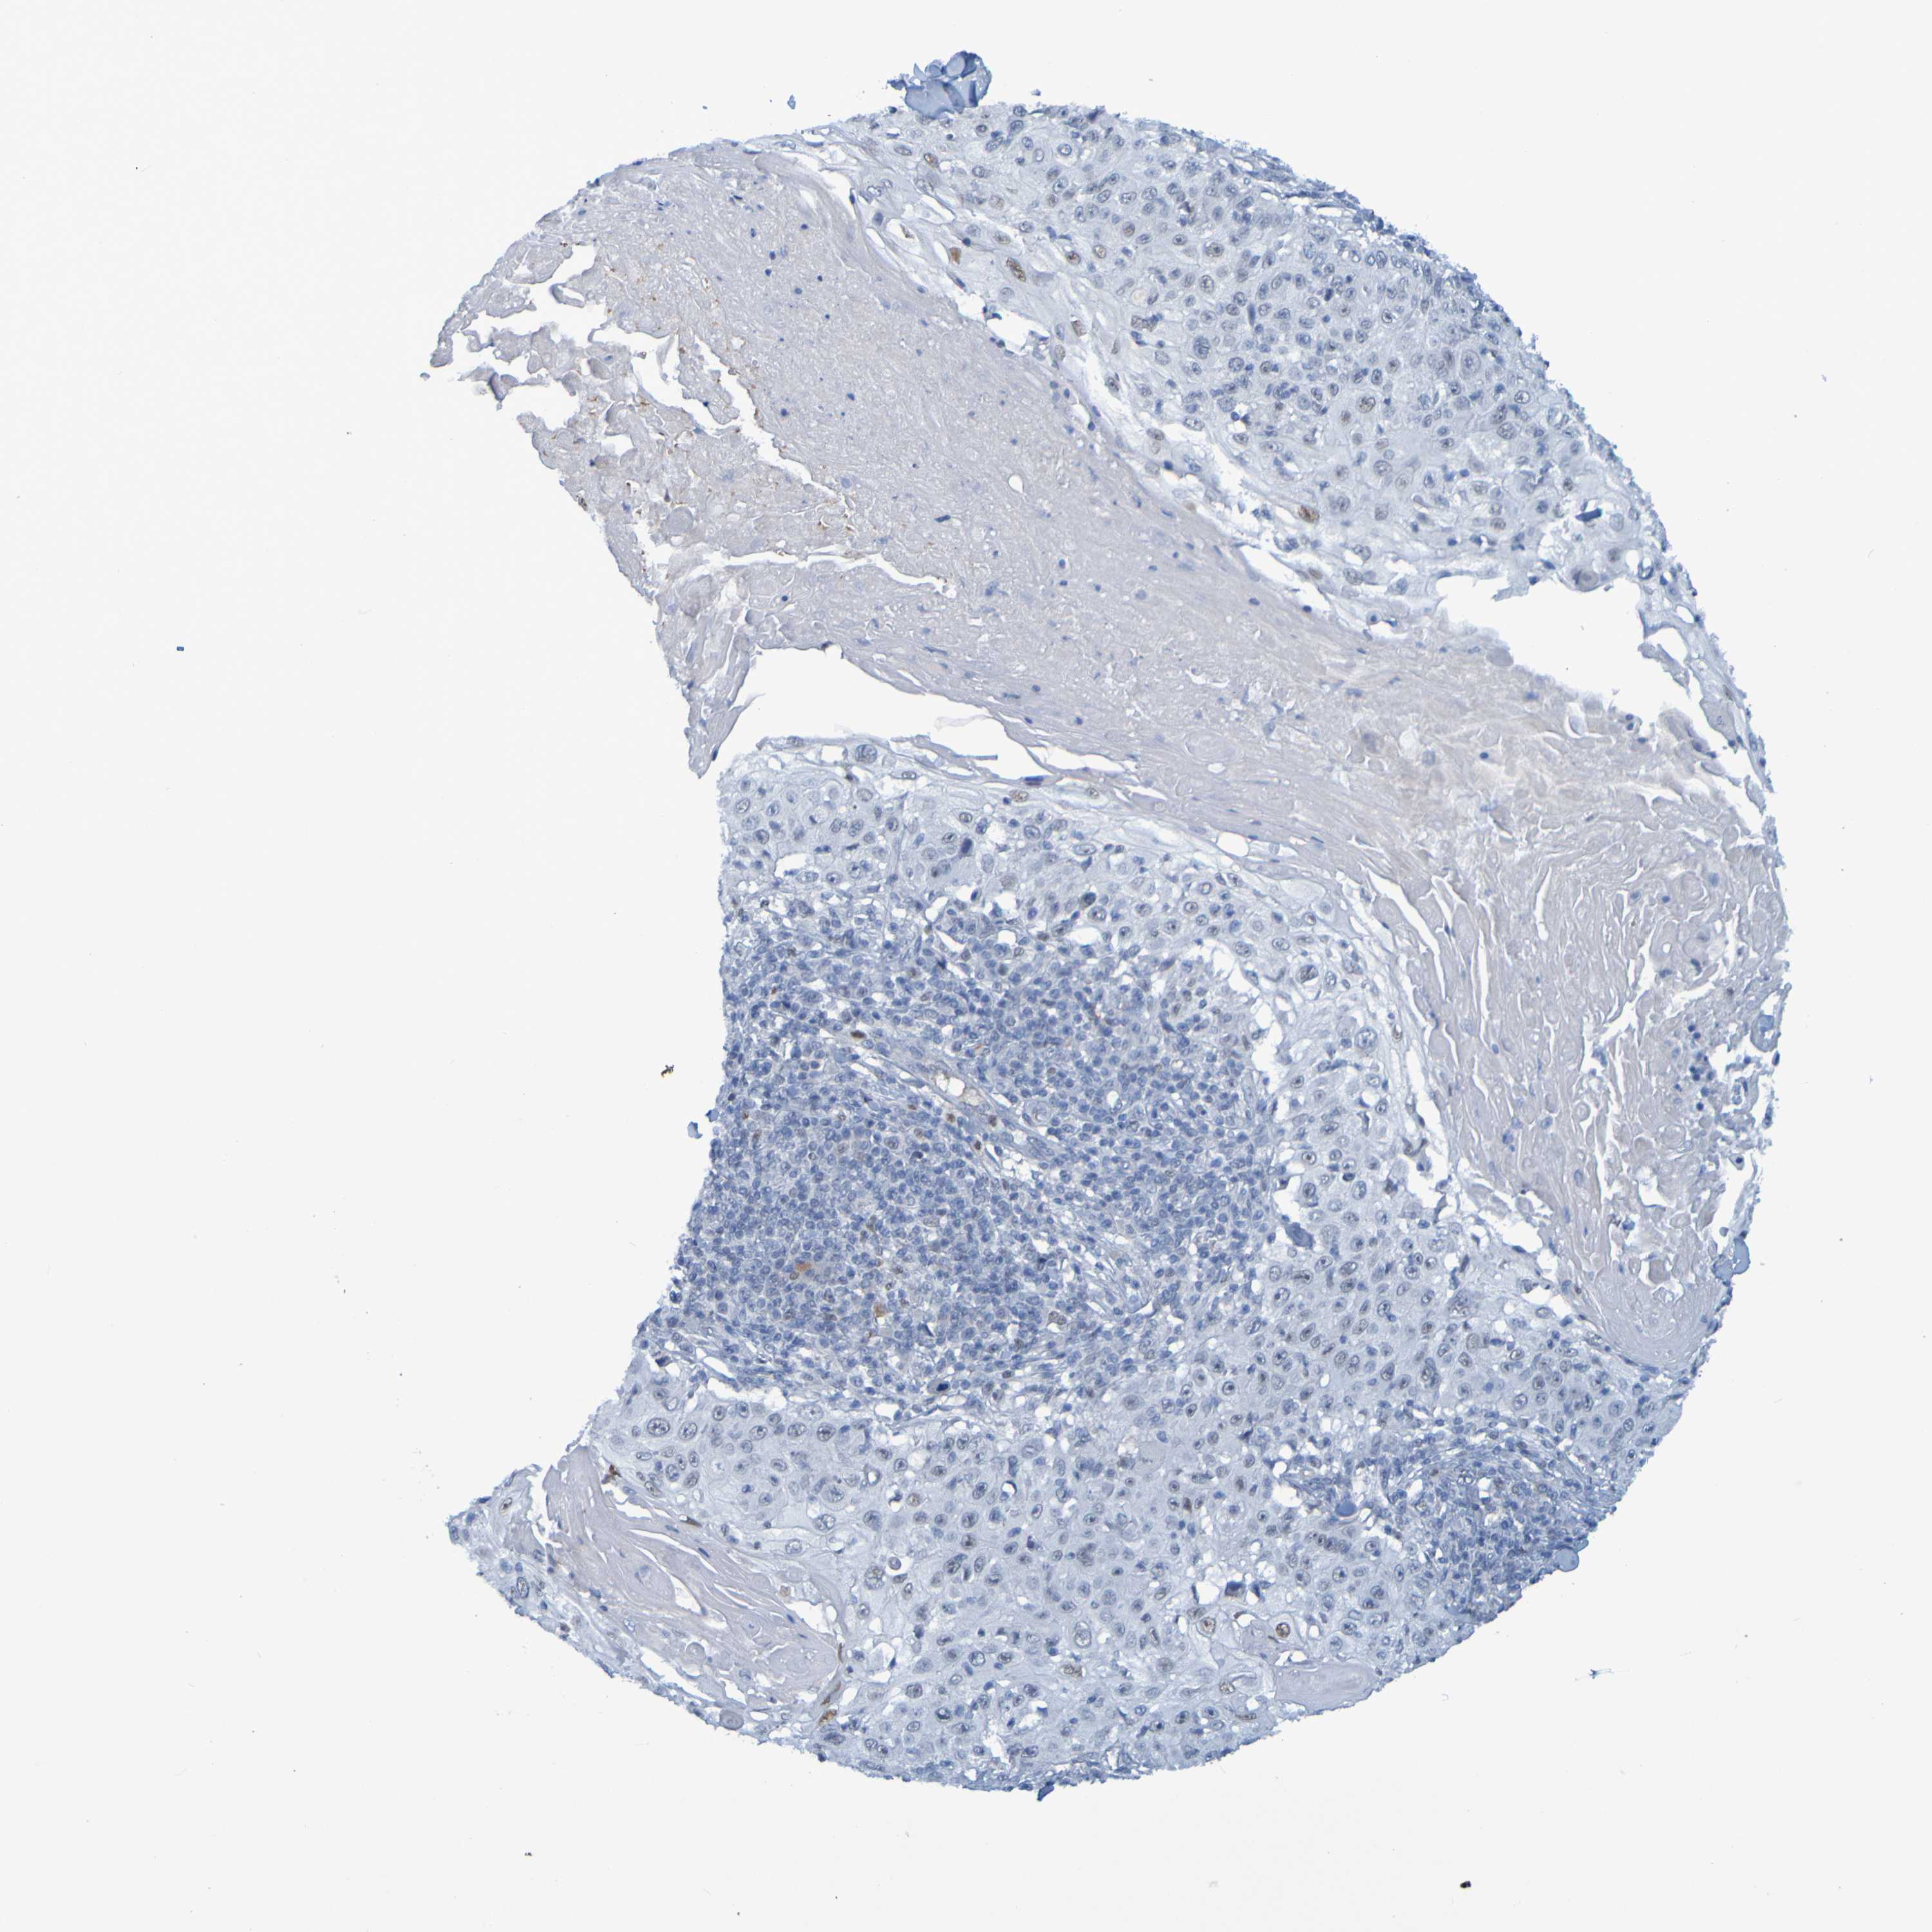

SKIN CANCER - Protein expressioni

A mouse-over function shows sample information and annotation data. Click on an image to view it in a full screen mode. Samples can be filtered based on level of antibody staining by selecting one or several of the following categories: high, medium, low and not detected. The assay and annotation is described here.

Each image is clickable and will lead to virtual microscopy that enables deeper exploration of all samples and also displays staining intensity scores, fraction scores and subcellular localization as well as patient and tissue information for each sample.

Antibody HPA012082

Staining

Medium

Intensity

Weak

Quantity

<25%

Location

None

Squamous cell carcinoma, NOS

Basal cell carcinoma

Adnexal tumor, benign